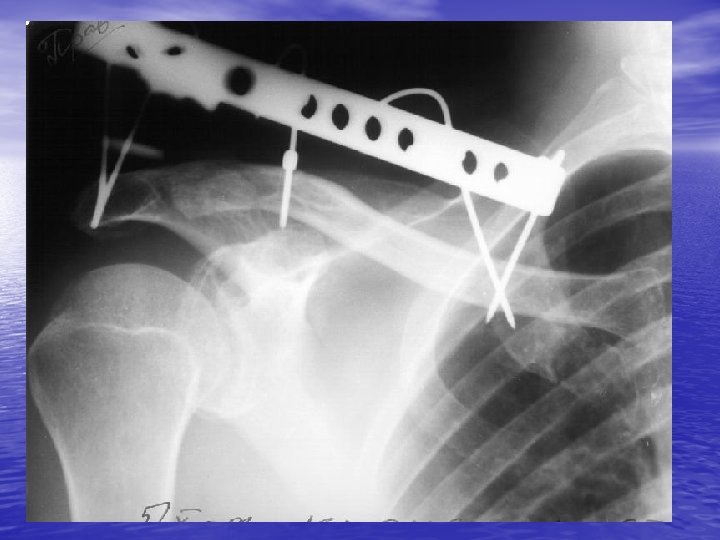

Neer Type II injury

Follow-up (3 year)